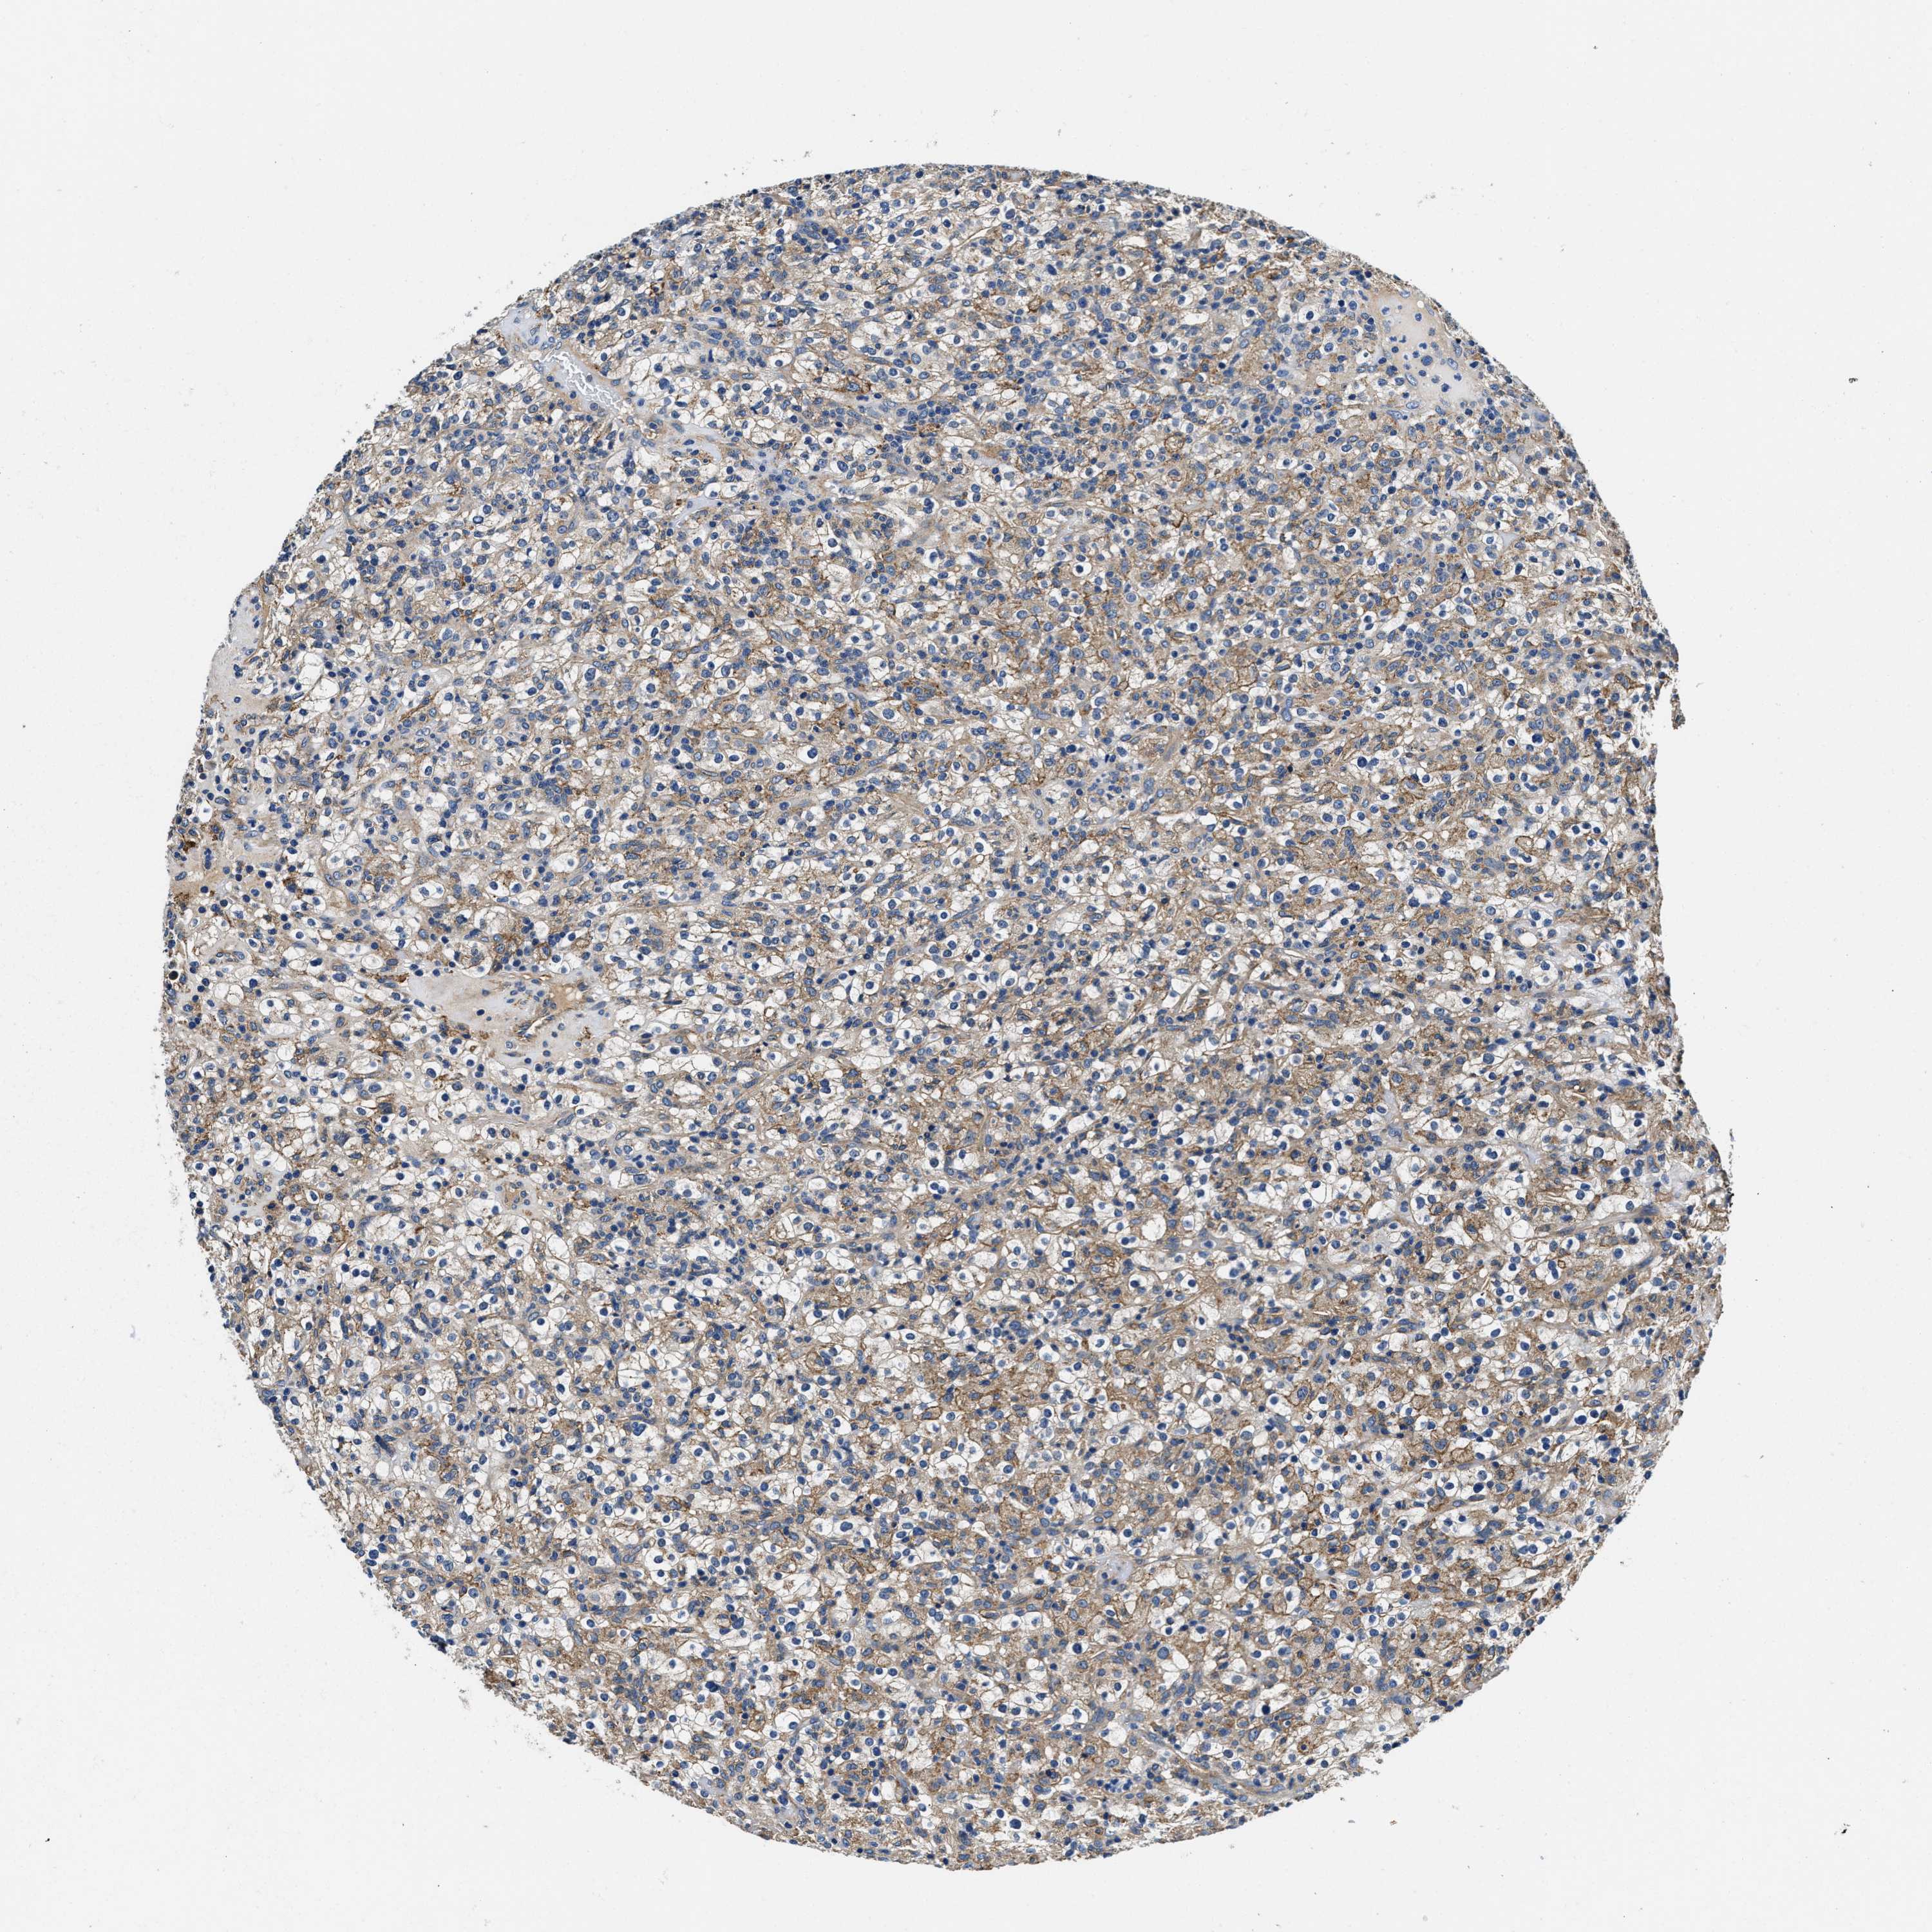

KIDNEY RENAL CLEAR CELL CARCINOMA (TCGA) - Interactive survival scatter ploti

The Survival Scatter plot shows the clinical status (i.e. dead or alive) for all individuals in the patient cohort, based on the same data that underlies the corresponding Kaplan-Meier plots. Patients that are alive at last time for follow-up are shown in blue and patients who have died during the study are shown in red.

ZFAND3 is potential prognostic, high expression is favorable in Kidney Renal Clear Cell Carcinoma (TCGA)

Best expression cut offi

: 37.15

Average pTPM 50.7

Number of samples 521